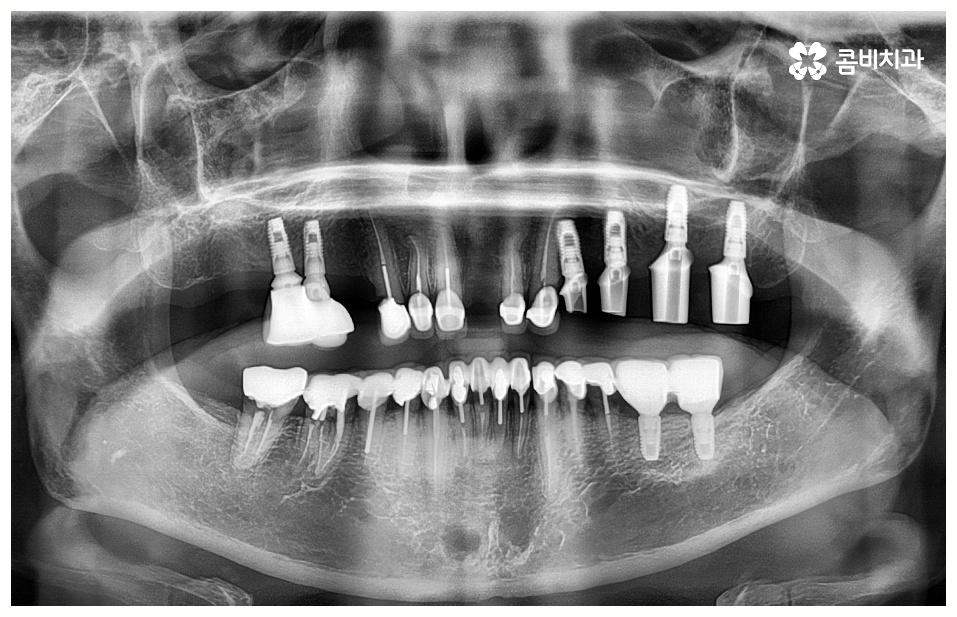

임플란트 시술을 받을 때 많은 분들이 궁금해 하시는 것 중 하나가 임플란트 치료기간 그리고 수명에 대한 것일 텐데요, 먼저 기간은 대략적으로 3~6개월 정도 걸린다고 알려져 있으나 환자마다 잇몸뼈 상황이나 전체적인 건강 상태 및 회복력이 다르기 때문에 환자분들에 따라 다르게 적용되고 있는 부분이고 그에 따라 임플란트 치료기간 또한 달라질 수 있습니다.

예를 들어서 잇몸뼈가 튼튼하다면 발치 후 즉시 임플란트 식립 시술을 할 수 있어서 임플란트 치료기간 이 줄어들고 보다 간편한 수복이 가능할 것이나 주변 잇몸에 염증이 남아있어서 먼저 치료를 해야 하거나 바탕이 되는 잇몸뼈의 밀도, 높이 등이 부족하여 보충이 필요한 경우에는 뼈이식 과정을 우선 진행해야 하기 때문에 임플란트 치료기간 이 길어질 수 있어요.

뼈이식은 각자에게 맞는 골이식재료 가루를 생리식염수에 반죽하여 빈 공간에 채워넣으면 이를 이용하여 우리의 세포가 잇몸뼈를 만들어내는 골융합 과정을 의미하는데 회복 시간을 충분히 주어 무리가 가지 않도록 진행을 해야 안정성과 지속성을 높일 수 있기 때문에 임플란트 치료기간 자체를 줄이는 데 초점을 맞추는 것보다는 필요한 처치들을 꼼꼼하게 해 주는 것에 초점을 맞추시는 게 필요할 거예요.

임플란트 치료는 자신의 자연 치아를 대신해 오랫동안 쓸 수 있도록 장기적인 안정성을 추구하는 것이 중요하기 때문에 최초의 진단과 치료 계획을 꼼꼼하게 세우는 것이 필수라고 할 수 있어요.